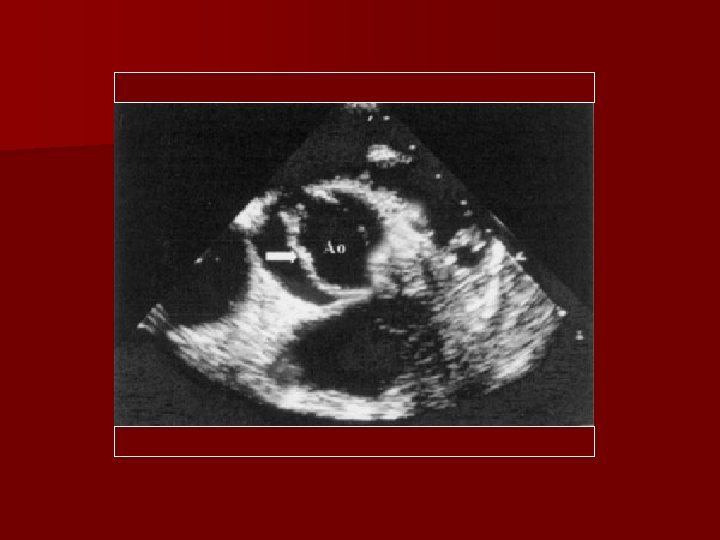

Imaging n Echocardiography – Modality of choice § Long-axis shows systolic doming due to limited valve opening § Short-axis allows examination of the commisures, leaflet morphology, and mobility.